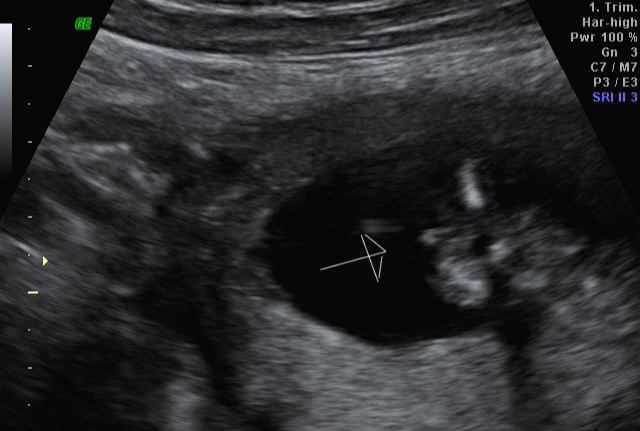

그리고 초음파 봐주시는 분께서 13주차가 되면 정확히 알 수 있으니 다음 주에 오라고 하셔서 일주일 뒤 다시 방문을 했습니다. (위에 사진은 12주 차 때 아들이라고 보여주신 초음파 사진이에요~ 화살표 보면 툭 튀어나와있는 부분을 보여주면서 아들이라고 하셨어요~)

아 진짜 전문가는 다르구나~ 이렇게 이른 주수에도 성별을 알 수가 있구나 생각을 했지만 이 시기 때는 성별을 정확히 알 수 없다는 글들을 봐서 살짝~ 의심스럽기도 했지만 그래도 100프로라니깐 ㅎㅎ 믿어보았어요~ 근데 위에 사진을 보면 성별을 알 수 있는 각도 법이 있는데 각도가 딸 같아서 긴가민가~하긴 했지만 의심은 잠시! 전문가 분을 믿기로 ㅋㅋㅋㅋ